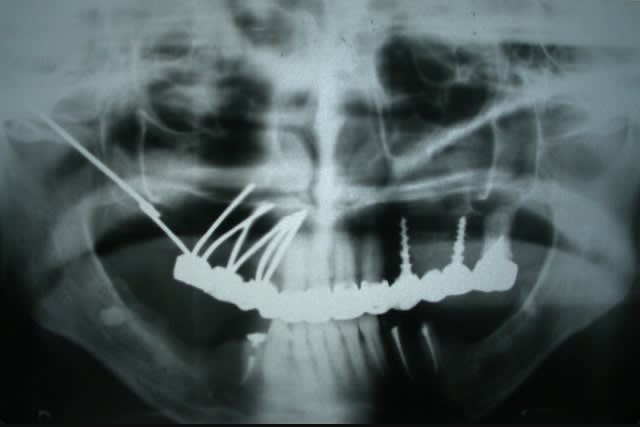

Tiens celle ci c'est pour pxav :

1970 Implant développé par les docteurs Roberts -> Implant ramique et symphysaire

pour moi, c'est du Tatum, si tu veux, il m'en reste un...mais à poser ça reste hot....

Img 5828 sggrfq - Eugenol

Img 5829 wayugg - Eugenol

Img 5830 vyxhar - Eugenol